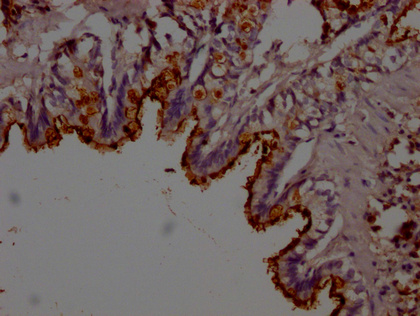

IHC image of CSB-PA012816LA01RA diluted at 1:200 and staining in paraffin-embedded rat lung tissue performed on a Leica BondTM system. After dewaxing and hydration, antigen retrieval was mediated by high pressure in a citrate buffer (pH 6.0). Section was blocked with 10% normal goat serum 30min at RT. Then primary antibody (1% BSA) was incubated at 4°C overnight. The primary is detected by a Goat anti-rabbit polymer IgG labeled by HRP and visualized using 0.05% DAB.